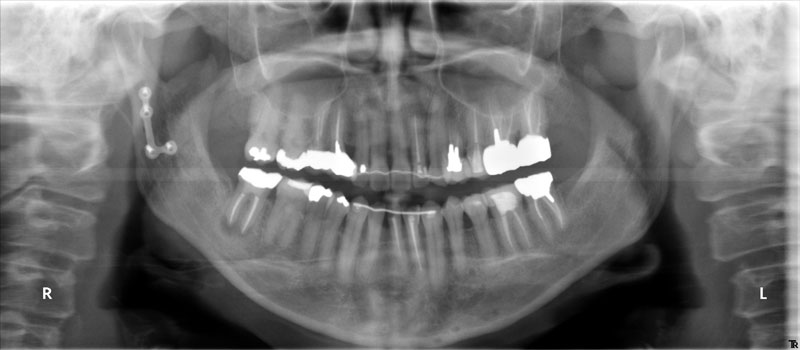

術前

- 初診:2006年。2010年―矯正治療を含めた一口腔単位の治療開始、治療当時、30代女性、喫煙者

- 矯正診断:3級骨格性の反対咬合

- 治療方針:以前に治療した歯の再治療(虫歯治療、歯内療法、歯周処置)、右下前歯1本抜歯、矯正用インプラントを用いたワイヤー矯正、修復処置(被せ物)、保定(上ワイヤー、下マウスピース)、歯茎のピーリング(漂白)、4か月メンテナンス

メンテナンスのみで、今のところ再治療を行った歯はありません。うまくコントロールされていると思います。ただ、鼻性由来の両側副鼻腔炎を患ってたので、耳鼻科への来院を促しました。